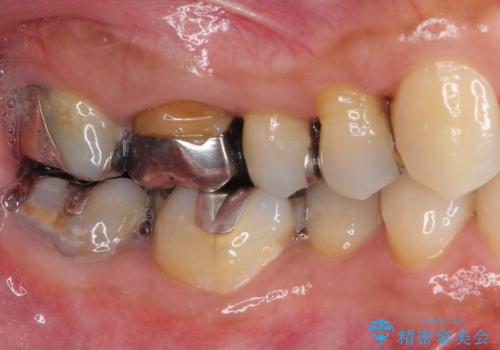

- 右上の小臼歯部に咬んだときに強い痛みを感じるとのことで来院された患者様です。

診査を行った結果、根管治療を行った後にオールセラミッククラウンにて補綴する治療計画となりました。

咬んだときの痛みに加えて夜間のズキズキする痛みもありましたが、1回目の根管治療実施後間もなく咬んだときの痛みがなくなったので、2回目に根管充填を行いました。